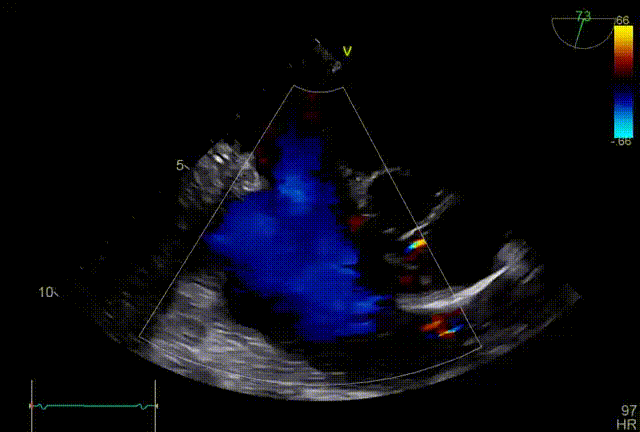

术前超声

术后超声